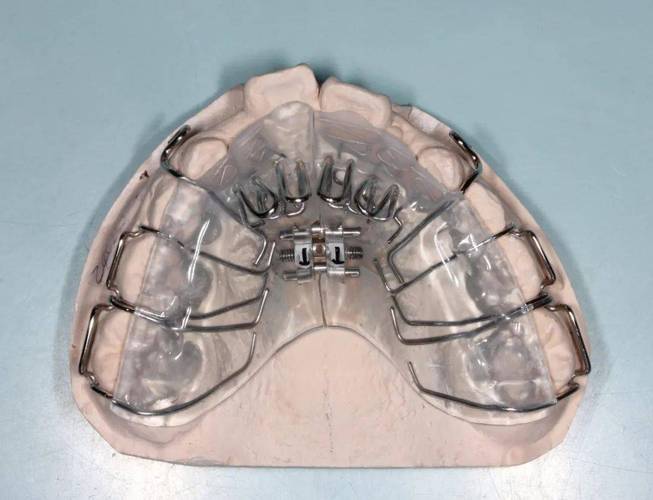

正畸方形勾托槽-图2

(图片来源网络,侵删)